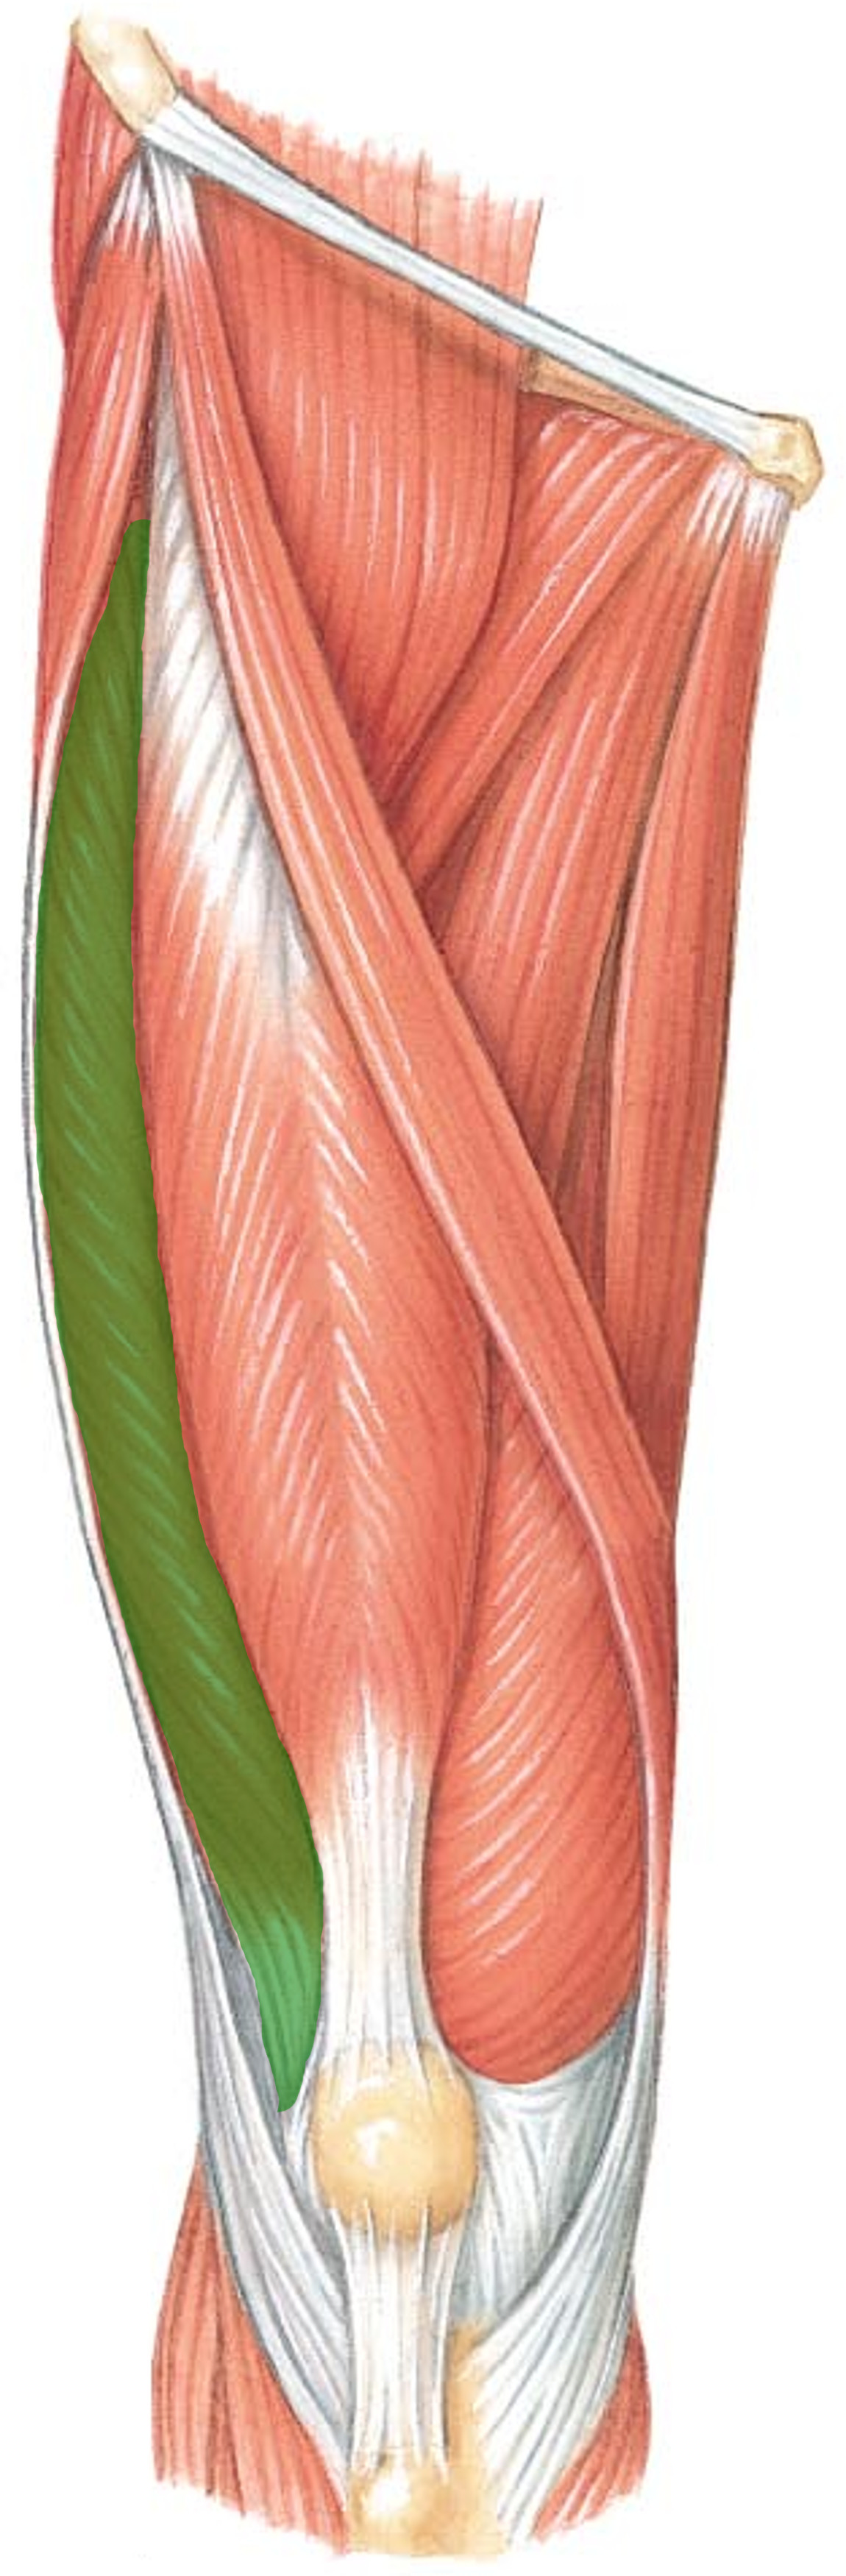

What is the innervation of this muscle?

Muscle - Rectus femoris

Femoral nerve L2-L4